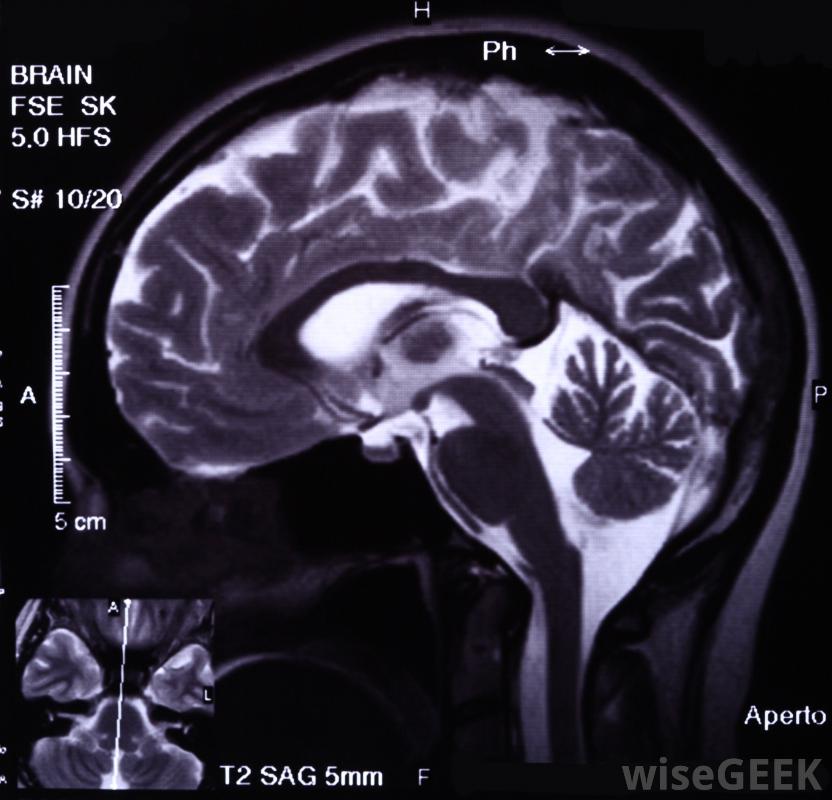

難治性癲癇是一種抵抗藥物治療的癲癇發作性疾病。臨床醫生和研究人員對如何定義難治性癲癇存在一些爭論。因此,這個術語有多種用法,當患者的癲癇被描述為難治性、耐藥或無反應時,建議詢問更多關于診斷的詳細信息,這將有助于患者理解護理人員得出的結論。醫生可以使用腦電圖來確認癲癇的診斷癲癇發作在普通人群中并不少見。人們可能只經歷一次發作,再也不會發作,尤其是在兒童早期。在其他人中,癲癇發作發展成癲癇,一種有多種形式的疾病。癲癇是根據患者發作的類型來分類的,也可以根據治療效果來分類。對藥物沒有反應的病人可能是癲癇手術的候選者。在一些病人中,盡管嘗試了幾種抗癲癇藥物,癲癇仍會持續,病人被稱為難治性癲癇。當病人在一段時間內經歷一次發作復發時,一些臨床醫生會做出這種診斷其他人可能會診斷難治性癲癇患者,如果在服藥和停藥時沒有明顯的差異。如果患者在服藥期間出現較少的癲癇發作,患者將不會被視為無反應者,因為他或她實際上對藥物有反應,盡管不完全CT掃描可用于調查患者的病因;難治性癲癇患者有可能開始對藥物產生反應并有所改善。相反,藥物治療效果好的患者可能會復發并發展為難治性癲癇。癲癇患者的治療因不遵守藥物治療方案而變得復雜。不按指示服藥的患者可能會出現癲癇發作,如果患者對不遵醫囑不誠實,醫生可能會認為患者患有難治性癲癇。癲癇根據患者經歷的癲癇發作類型進行分類,也可以根據其對治療的反應程度進行分類癲癇發作早、發育遲緩、神經系統檢查異常、癲癇叢集以及在治療開始前多次發作的人患難治性癲癇的風險增加對藥物治療無反應的癲癇患者可以選擇生酮飲食、癲癇手術,或迷走神經刺激。一旦發現患者對多種抗癲癇藥物無反應,這些治療方法可能成為可能的選擇。通常這類患者會去癲癇門診,接受癲癇專科醫生的治療,該專家可以提供最新的研究和治療方案患有難治性癲癇的人可能需要因突發性癲癇發作而進行緊急醫療。癲癇是根據一個人經歷的癲癇發作次數和對治療的反應程度來分類的。難治性癲癇對藥物治療有抵抗力大多數癲癇發作是由大腦的電異常引起的。